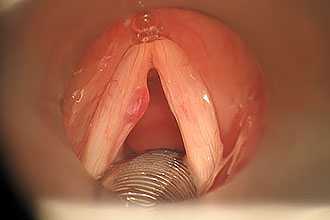

Уточнить аллергический ларингит, его характер поражения и локализацию возможно посредством ларингоскопии. Для такой природы поражения характерна бледность слизистых оболочек, в отличие от ее гиперемии при воспалительных процессах, обусловленных инфекционными агентами. При этом может отмечаться выраженный отек гортани.

Диагностика проводится с помощью ларингоскопии, при которой специалист визуализирует покраснение, отечность связок, на поверхности которых отмечается мокрота. При гриппе на связках возможны кровоизлияния. Для определения инфекционного возбудителя проводится бактериологическое исследование, материал для которого собирается со слизистой ротоглотки. В анализах крови регистрируется лейкоцитоз.

При хронической форме при ларингоскопии наблюдается гиперпластический или атрофический тип болезни. У вокалистов, воспитателей и дикторов на поверхности утолщенных связок визуализируются узелки.